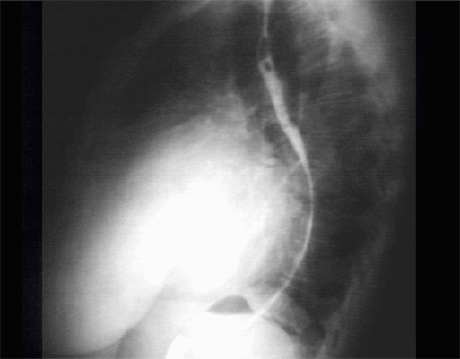

Lat

The lateral view with barium swallow, demonstrates marked posterior displacement of the esophagus by the giant left atrium.